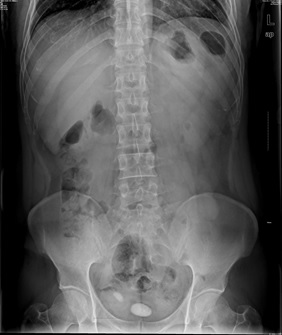

05卷-4.男,55岁,反复尿频、尿痛、排尿困难半年(本题满分2.00分)

本题答案:B

题目解析:【该题针对“X线-泌尿系结石”知识点进行考核】